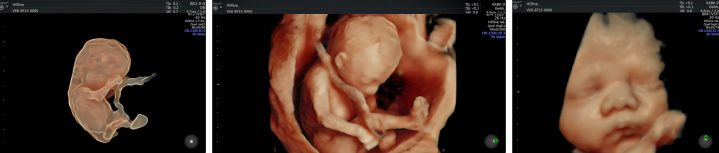

4Dエコー[超音波]

当クリニックでは、お腹の中の赤ちゃんの様子をリアルタイムで詳しく診ることのできる4Dエコーを導入しております。

4Dエコーとは、3D超音波画像に時間軸を加えたものです。

お母さんのお腹にいる赤ちゃんの動きや表情を見ることができるので、わが子を実感していただけます。

また、詳しく様子を見ることで、安全なお産をサポートします。

エコー画像